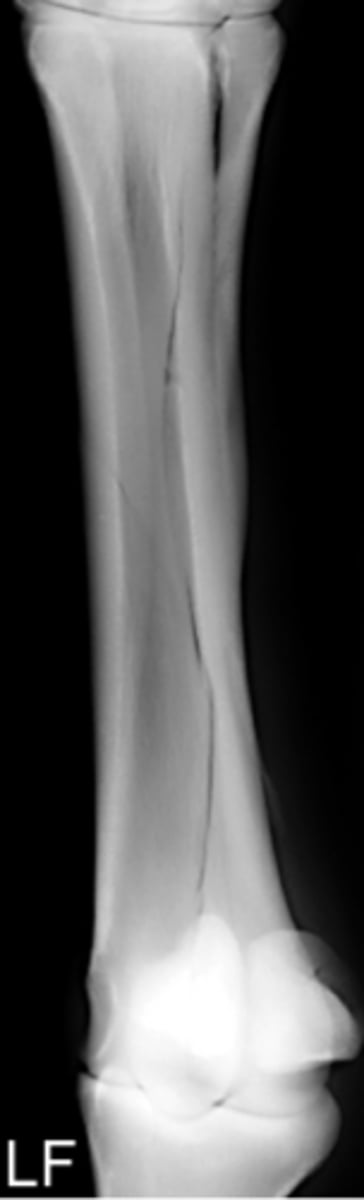

What is this an example of?

Malunion

What is a malunion?

the healing of a bone in a nonanatomic position